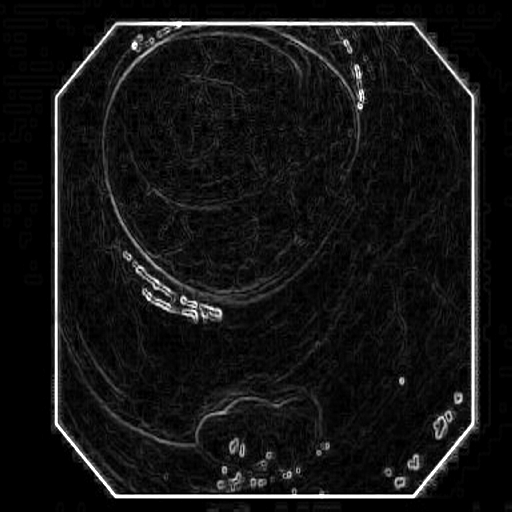

(a) Polyp 1

Refer to caption

(b) Sobel x

(c) Sobel y

(d) Sobel xy

(e) Polyp 2

(f) Sobel x

(g) Sobel y

(h) Sobel xy

Fig. 3: Edge maps of the Sobel operator in x-y directions

The Edge-Guided Feature Enrichment (EGFE) unit actively enhances feature representation by integrating edge knowledge into the set of features. It applies a Sobel operator to the input feature set, generating separate gradient magnitude maps for horizontal (𝒮x)subscript𝒮𝑥(\mathcal{S}_{x})( caligraphic_S start_POSTSUBSCRIPT italic_x end_POSTSUBSCRIPT ) and vertical (𝒮y)subscript𝒮𝑦(\mathcal{S}_{y})( caligraphic_S start_POSTSUBSCRIPT italic_y end_POSTSUBSCRIPT ) directions (Fig. 3). As illustrated in Fig. 3, the Sobel operation in a single direction captures limited information about the polyp. However, combining these maps (Fig. 3(d) and Fig. 3(h)) effectively captures polyp boundaries and enriches learned features. The final gradient magnitude map, produced using the Euclidean norm (Eq. 1), highlights regions with significant intensity changes at polyp boundaries.